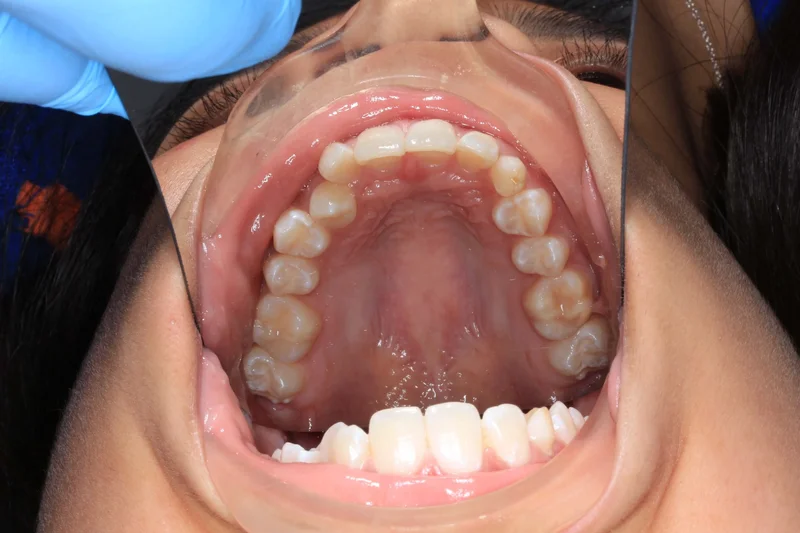

Upper Occlusal

Upper Occlusal - Before Treatment

Before

Upper Occlusal - After Treatment

After